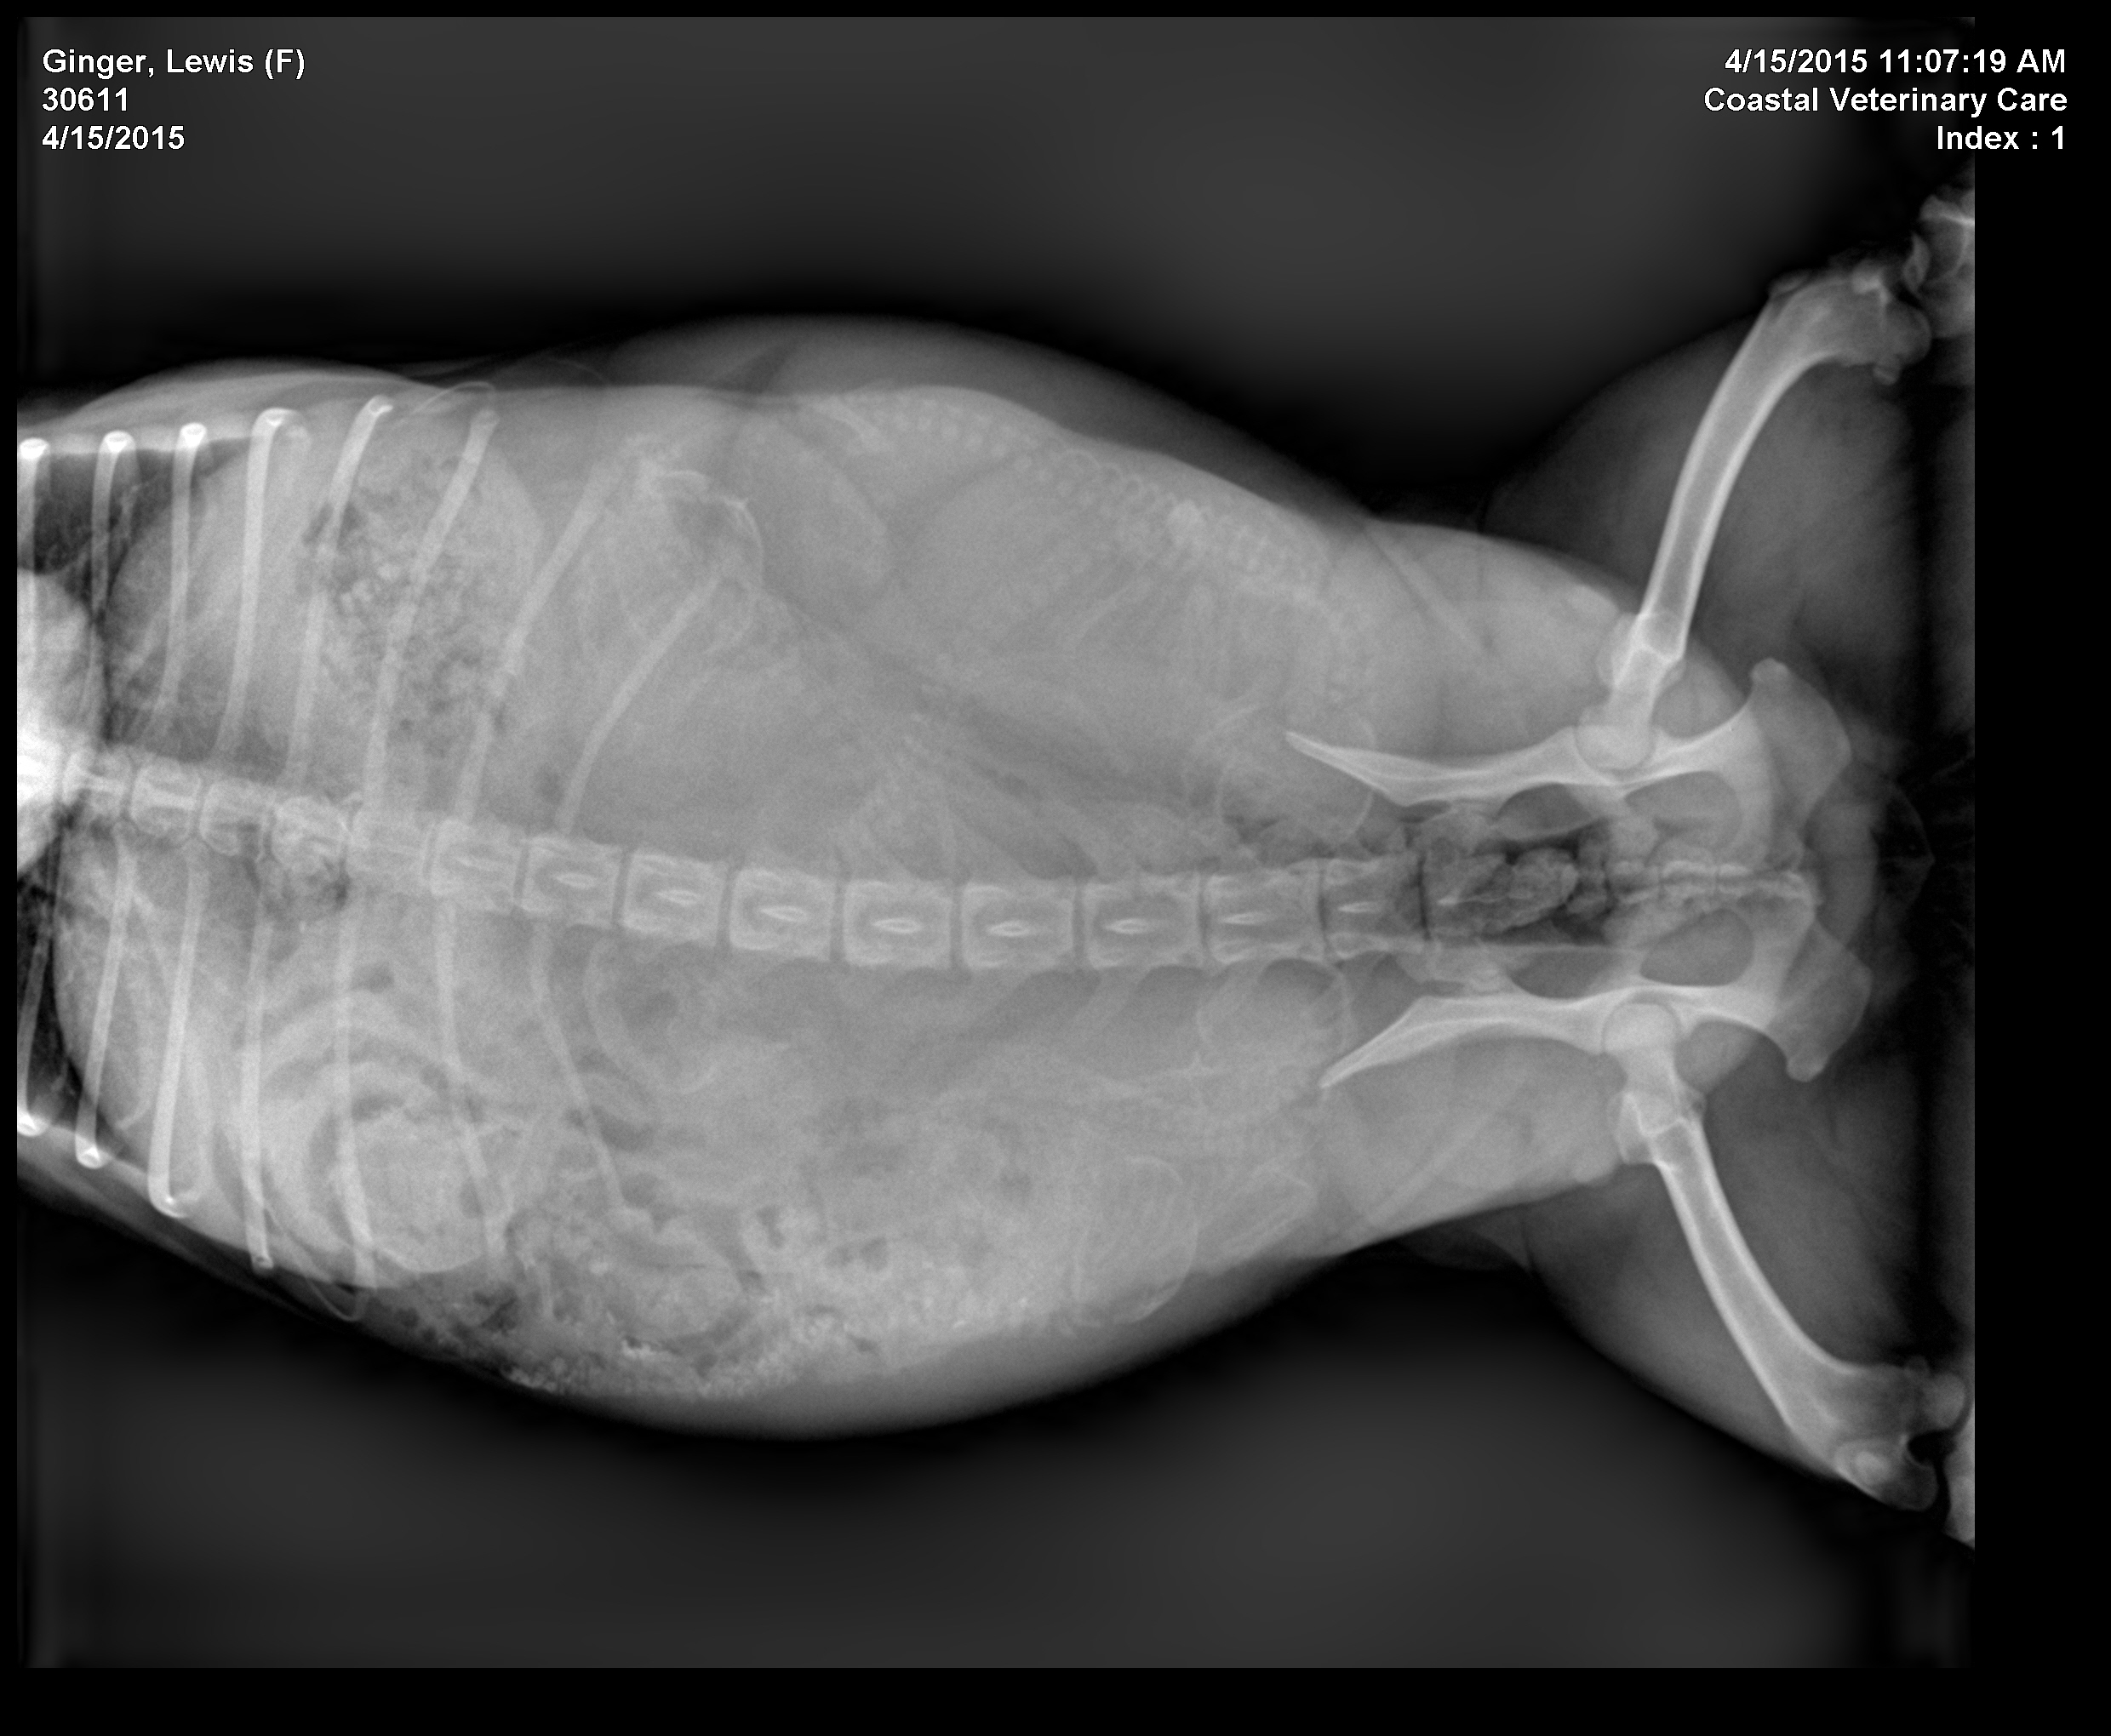

Vet says 6, I see 5. Anyone else want to take a guess???

i think 6 2 males 4 females we love seing all the puppes we have a mini aussies female.